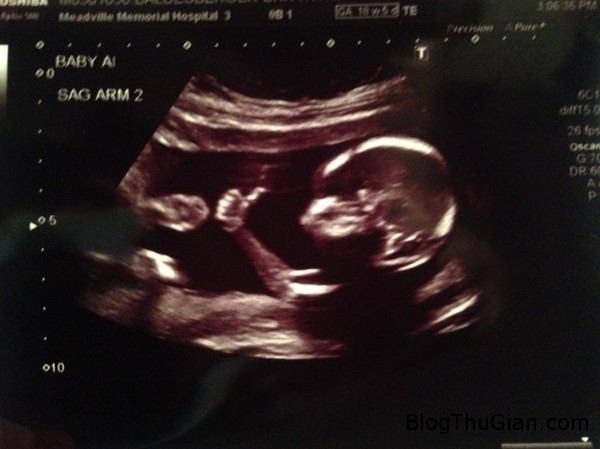

Hình ảnh siêu âm cho thấy em bé nằm trong bụng mẹ này đã được đặt biệt danh là “Em bé Fonz”

Được chia sẻ trên trang mạng xã hội Reddit, bức ảnh bào thai giơ ngón tay cái ngộ nghĩnh do một thành viên có tên Adam, 25 tuổi đăng tải đã khiến cộng đồng mạng không giấu nổi sự thích thú và tranh nhau đưa ra những bình luận hài hước.

Em bé Fonz tạo dáng với kiểu giơ ngón tay cái.

Hình ảnh siêu âm cho thấy em bé nằm trong bụng mẹ này đã được đặt biệt danh là “Em bé Fonz” dựa theo kiểu pose hình giơ ngón tay cái đặc trưng của nhân vật Fonz trong bộ phim sitcom nổi tiếng “Happy Days” (Những ngày vui vẻ) của Mỹ.

Anh Adam, 25 tuổi – bố của em bé tự hào cho biết anh vẫn chưa biết giới tính của em bé mặc dù vừa mới siêu âm vào ngày 27/8 vừa qua. Anh cũng tiết lộ thêm, người bạn đời của mình vẫn hy vọng mang thai đôi, dự kiến em bé sẽ chào đời vào tháng 1/2015.